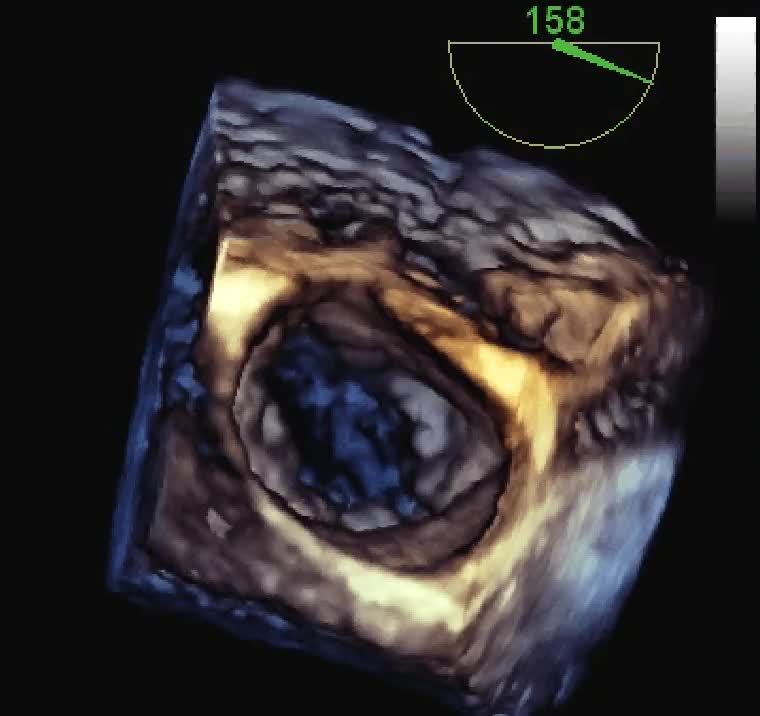

Endocardite infettiva della valvola tricuspide

Autore:

Andrea Barbieri